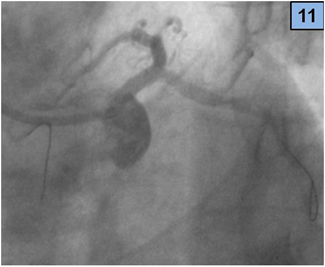

4. A 3.5 x 18 mm zotarolimus DES was placed from medium LM to proximal LAD artery through the LM – CX stent (Figure 10), and a new guidewire was recrossed to the CX (Figure 11).

Figure 11 The wire in the CX was recrossed.